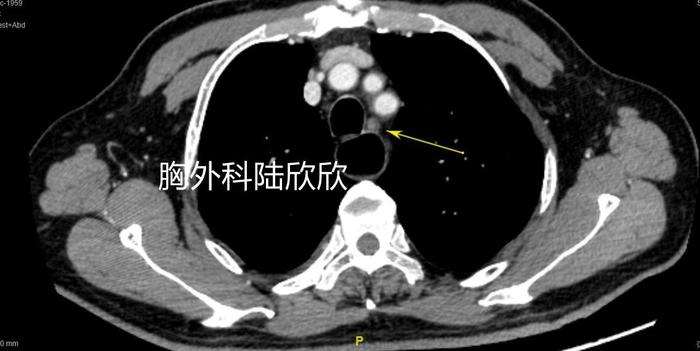

上图,脊柱前扩张的近端食管,扩张明显,内部有食物和粘液。肿瘤近端的食管明显扩张增粗。对于消化道肿瘤来说,只要是肿瘤引起的梗阻比较厉害,肿瘤近端的消化道管腔扩张就比较厉害。

上图,可见右上肺一个12毫米的混合磨玻璃结节,结节的实性成分像海里的珊瑚礁。上面两张图同时可见肺结节平面的食管近端扩张。